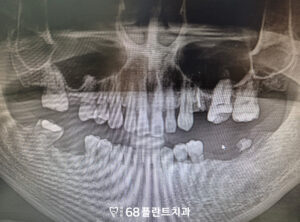

◆ 전 > 후 ◆

치료가 모두 마무리된 후

환자분께서는 그동안 여러 개의 치아가 상실되어

제대로 씹지 못하고 식사할 때마다

불편함을 느끼셨지만,

임플란트 치료와 상악동거상술을 통해

이제는 다양한 음식을 골고루 드실 수 있게 되었다며

큰 만족감을 표현하셨습니다.